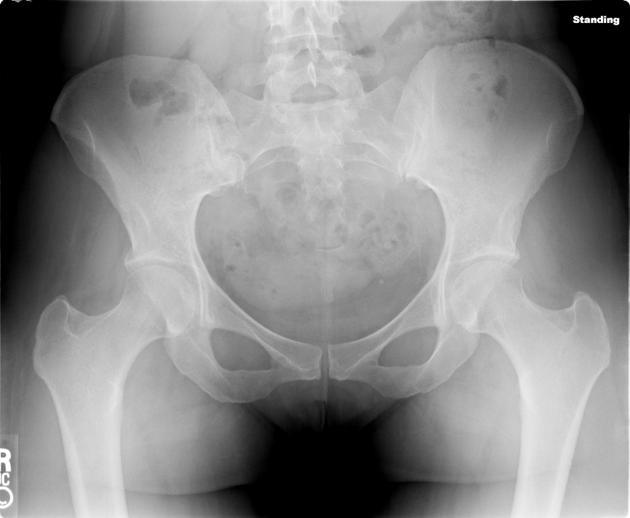

PXR for the case found here:

(PXR source: http://radiopaedia.org/articles/pelvis-1)